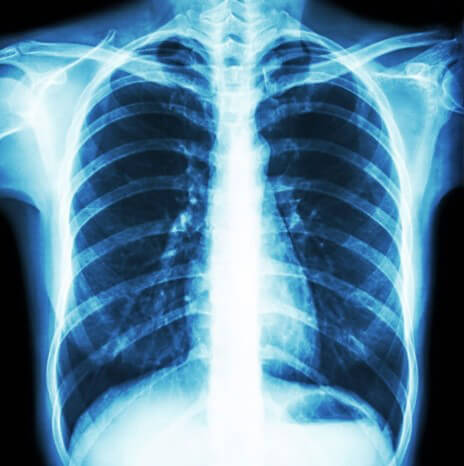

Moreover, this image is an example of an abdominopelvic X-ray on a hypersthenic patient. It shows poor penetration and poor optical density.

And finally, we can see here an example of an abdominopelvic X-ray showing proper optical density, penetration, and organ size, shape, and alignment.